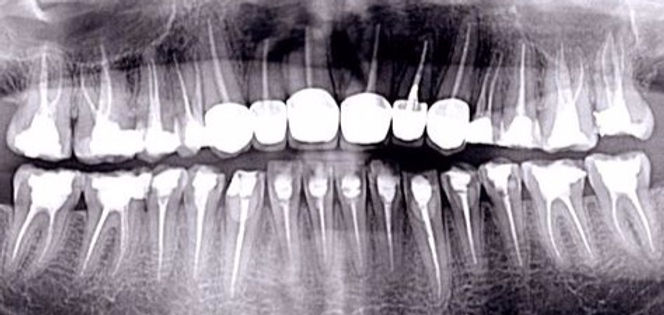

Root canal treatment (Endodontics) is needed when the blood or nerve supply of the tooth (called the ‘pulp') is infected through decay or injury. This does not necessarily result in pain or swelling in the initial stages and often goes unnoticed until symptoms.

The aim of the treatment is to remove all the infection from the nerve canal. The root is cleaned and filled to prevent further infection. The treatment is a skilled and time-consuming procedure so most courses of treatment will involve two or more visits to your dentist.